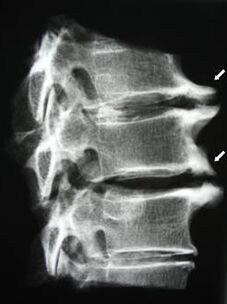

Nelle fasi iniziali, l'osteocondrosi viene rilevata mediante risonanza magnetica. Successivamente, la patologia può essere diagnosticata mediante radiografia. Nelle radiografie della colonna cervicale, diventano evidenti una diminuzione della distanza tra le vertebre, cambiamenti patologici nelle articolazioni delle faccette e osteofitosi.

| Osteocondrosi cervicale | La comparsa di cambiamenti patologici in uno o più segmenti di movimento spinale. Mobilità spinale compromessa, sviluppo di sindromi dolorose miofasciali e pizzicamento delle radici spinali | Dolore, parestesie e disturbi motori nella regione cervicale, che si estendono alla parte posteriore della testa e agli arti superiori. Rilevazione di cambiamenti caratteristici nella colonna vertebrale alla risonanza magnetica e alle radiografie (osteofiti, diminuzione della distanza tra le vertebre, segni di danno alle articolazioni intervertebrali) |